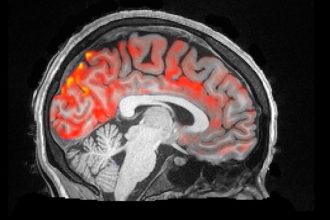

Si duket shpëlarja e vërtetë e trurit?

Mbase këtë nuk e keni ditur, mirëpo organizmi ynë çdo natë shpëlan…